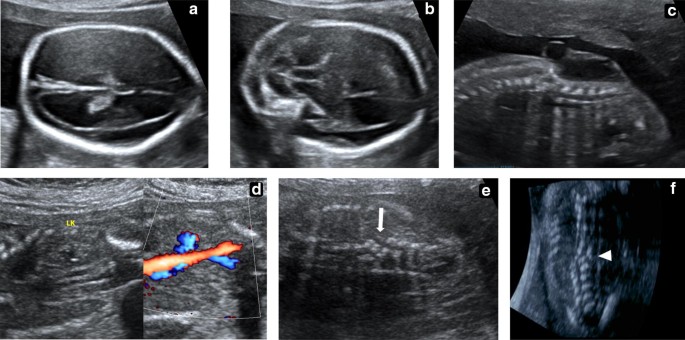

سونوگرافی (Ultrasound): سونوگرافی میتواند تصویر جنین در حال رشد را مشاهده کرده و علائم فیزیکی NTDs را شناسایی کند.